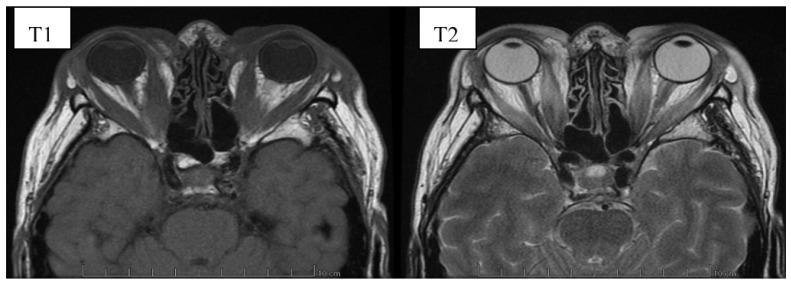

(1) Background: Graves' orbitopathy (GO) is an autoimmune inflammation of the orbital tissues and the most common extra-thyroid symptom of Graves' disease (GD). Mild cases of GO are often misdiagnosed, which prolongs the diagnostic and therapeutic process, leading to exacerbation of the disease. A severe course of GO may cause permanent vision loss. (2) Methods: The article presents an analysis of GO-its etiopathogenesis, diagnostics, current treatment and potential future therapeutic options based on a review of the currently available literature of the subject. (3) Results: Current treatment of the active GO consists predominantly in intravenous glucocorticoids (GCs) administration in combination with orbital radiotherapy. The growing knowledge on the pathogenesis of the disease has contributed to multiple trials of the use of immunosuppressive drugs and monoclonal antibodies which may be potentially effective in the treatment of GO. Immunosuppressive treatment is not effective in patients in whom a chronic inflammatory process has caused fibrous changes in the orbits. In such cases surgical treatment is performed-including orbital decompression, adipose tissue removal, oculomotor muscle surgery, eyelid alignment and blepharoplasty. (4) Conclusions: Management of GO is difficult and requires interdisciplinary cooperation in endocrinology; ophthalmology, radiation oncology and surgery. The possibilities of undertaking a reliable assessment and comparison of the efficacy and safety of the therapeutic strategies are limited due to the heterogeneity of the available studies conducted mostly on small group of patients, with no comparison with classic systemic steroid therapy. The registration by FDA of Teprotumumab, an IGF1-R antagonist, in January 2020 may be a milestone in future management of active GO. However, many clinical questions require to be investigated first.

(1)背景:格雷夫斯眼眶病(GO)是眼眶组织的自身免疫性炎症,是格雷夫斯病(GD)最常见的甲状腺外症状。轻度GO病例常被误诊,这延长了诊断和治疗过程,导致病情加重。严重的GO病程可能导致永久性视力丧失。(2)方法:本文基于对该主题现有文献的综述,对GO的病因发病机制、诊断、当前治疗及未来潜在治疗选择进行了分析。(3)结果:目前对活动性GO的治疗主要包括静脉注射糖皮质激素(GCs)联合眼眶放疗。对该疾病发病机制的认识不断增加,促使人们对免疫抑制药物和单克隆抗体进行了多项试验,这些药物可能对GO治疗有效。免疫抑制治疗对慢性炎症过程导致眼眶纤维改变的患者无效。在这种情况下,进行手术治疗,包括眼眶减压、脂肪组织切除、动眼肌手术、眼睑整复和眼睑成形术。(4)结论:GO的管理具有挑战性,需要内分泌学、眼科、放射肿瘤学和外科的多学科合作。由于现有研究大多在小群体患者中进行,且未与经典全身类固醇疗法进行比较,因此对治疗策略的疗效和安全性进行可靠评估和比较的可能性有限。2020年1月,IGF1-R拮抗剂替普罗单抗获得美国食品药品监督管理局(FDA)批准,这可能是未来活动性GO管理的一个里程碑。然而,许多临床问题仍需首先进行研究。